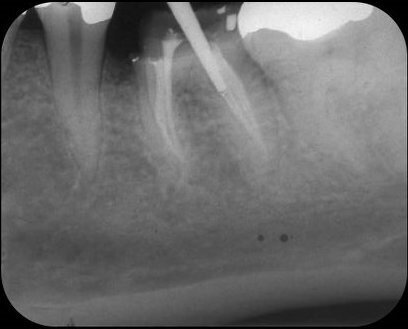

Als jonge tandarts was ik volkomen ontdaan over deze iatrogene complicatie. Er waren in 1982 geen speciale cementen beschikbaar om een perforatie te sluiten, en dus besloot ik om het defect tijdelijk af te sluiten met amalgaam. De twee mesiale en twee distale kanalen werden met handvijlen geprepareerd, en de kanalen werden geïrrigeerd met 2,5% natriumhypochloriet. Daarna vulde ik de kanalen door middel van laterale condensatie met gutta-percha en AH26, waarbij in het distolinguale kanaal ruimte werd gemaakt voor een wortelstift (afb. 3). Volgens de toen geldende inzichten was een gegoten opbouw geïndiceerd alvorens er een volledige gouden kroon geplaatst zou worden.

Afb. 3: Kanaalvulling aanbracht en perforatie afgesloten met amalgaam